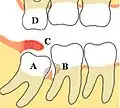

Некоторые проблемы, которые могут возникнуть или не возникнуть с третьими молярами: A Мезиоретинированный, частично прорезавшийся третий моляр нижней челюсти; B Кариес зубов и дефекты пародонтита, связанные как с третьими, так и со вторыми молярами, вызвано упаковкой пищевых продуктов и плохим доступом к методам гигиены полости рта; C Воспалённая покрышка, покрывающая частично прорезавшийся третий нижний моляр, со скоплением остатков пищи и бактерий под ним; D Верхний третий моляр перерос, разрывается из-за отсутствия контакта с противоположным зубом и может начать травматически окклюзию в крышечку над нижним третьим моляром. Зубы без сопротивления обычно острые, потому что они не притуплены другим зубом.